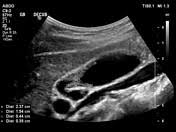

Résumé l'adénomyomatose (adm) vésiculaire est une anomalie bénigne, acquise, caractérisée par une hypertrophie de la muqueuse s'invaginant au sein d'une musculeuse épaissie (sinus de.

Il existe trois formes d'adm : This makes the uterine walls grow thicker. Segmentaire, fundique et plus rarement diffuse. Adenomyosis is a condition that involves the encroachment, or movement, of the endometrial tissue that lines the uterus into the muscles of the uterus. The exact cause of adenomyosis is unknown, but it is thought that endometrial glands directly invade the myometrium resulting in spiral vessel angiogenesis, and adjacent smooth muscle hyperplasia and hypertrophy.